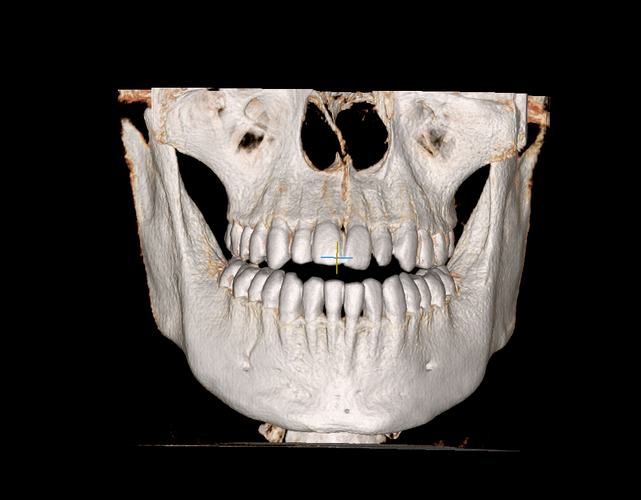

My maxillofacial surgeon said there are no problems and the solution depends on the bite and teeth

file_000000006a7871fa99715793c50dc5a4.png631.1 KB · Views: 0

file_000000006a7871fa99715793c50dc5a4.png631.1 KB · Views: 0 -